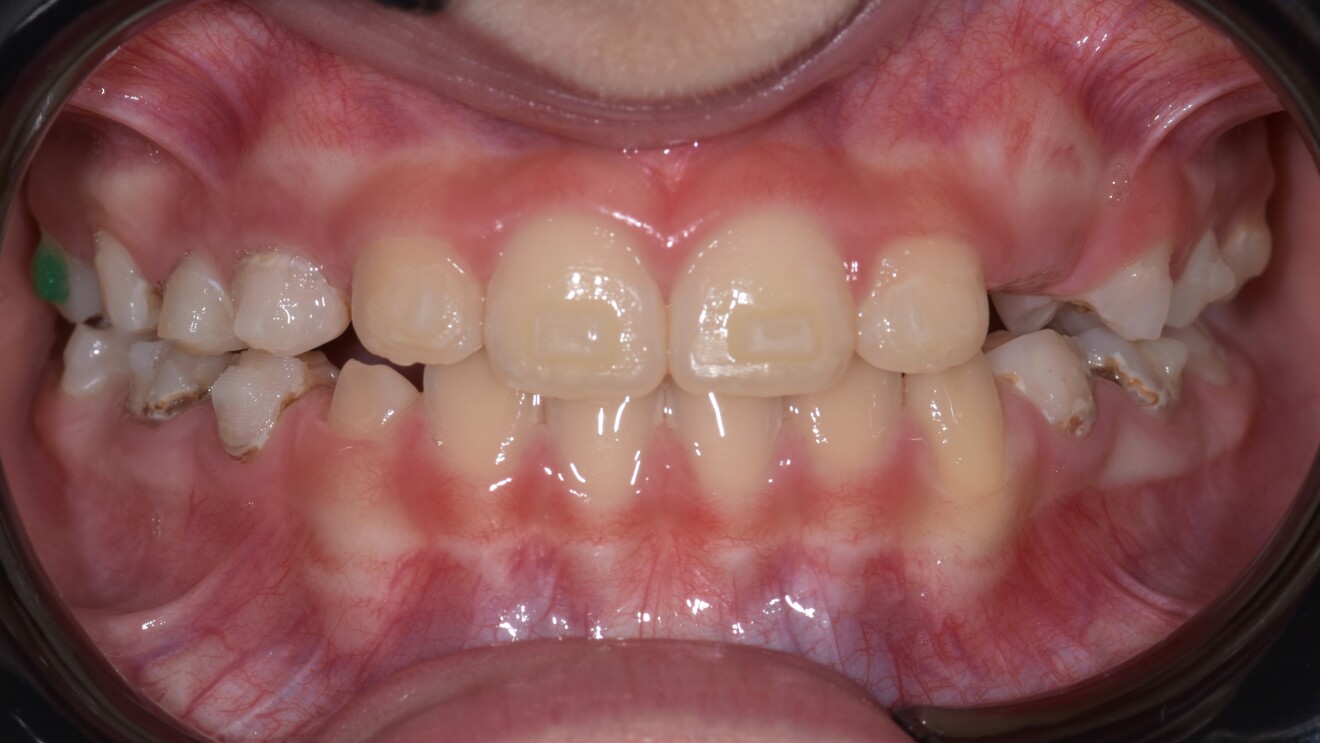

Figs. 1d–h: Pre-treatment records. Intra-oral photographs.